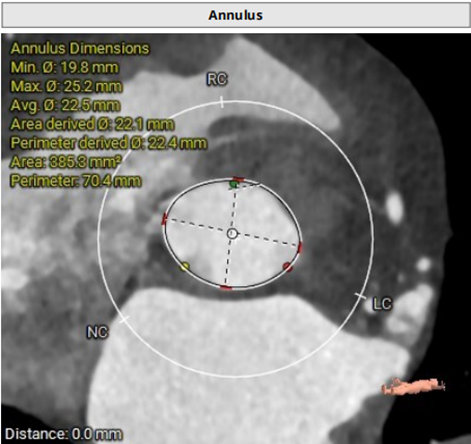

术前CT评估

三叶瓣,主动脉瓣环直径22.4mm;瓣环长短径分别为25.2*19.8mm,周长为70.4mm,面积为385.3mm²。左室流出道21.2mm,法式窦28.3mm*28.1mm*28.9mm;

左冠高度11.7mm,右冠高度13.8mm;窦管交界 26.0mm,升主动脉直径33.3mm。

主动脉瓣瓣环直径22.4mm